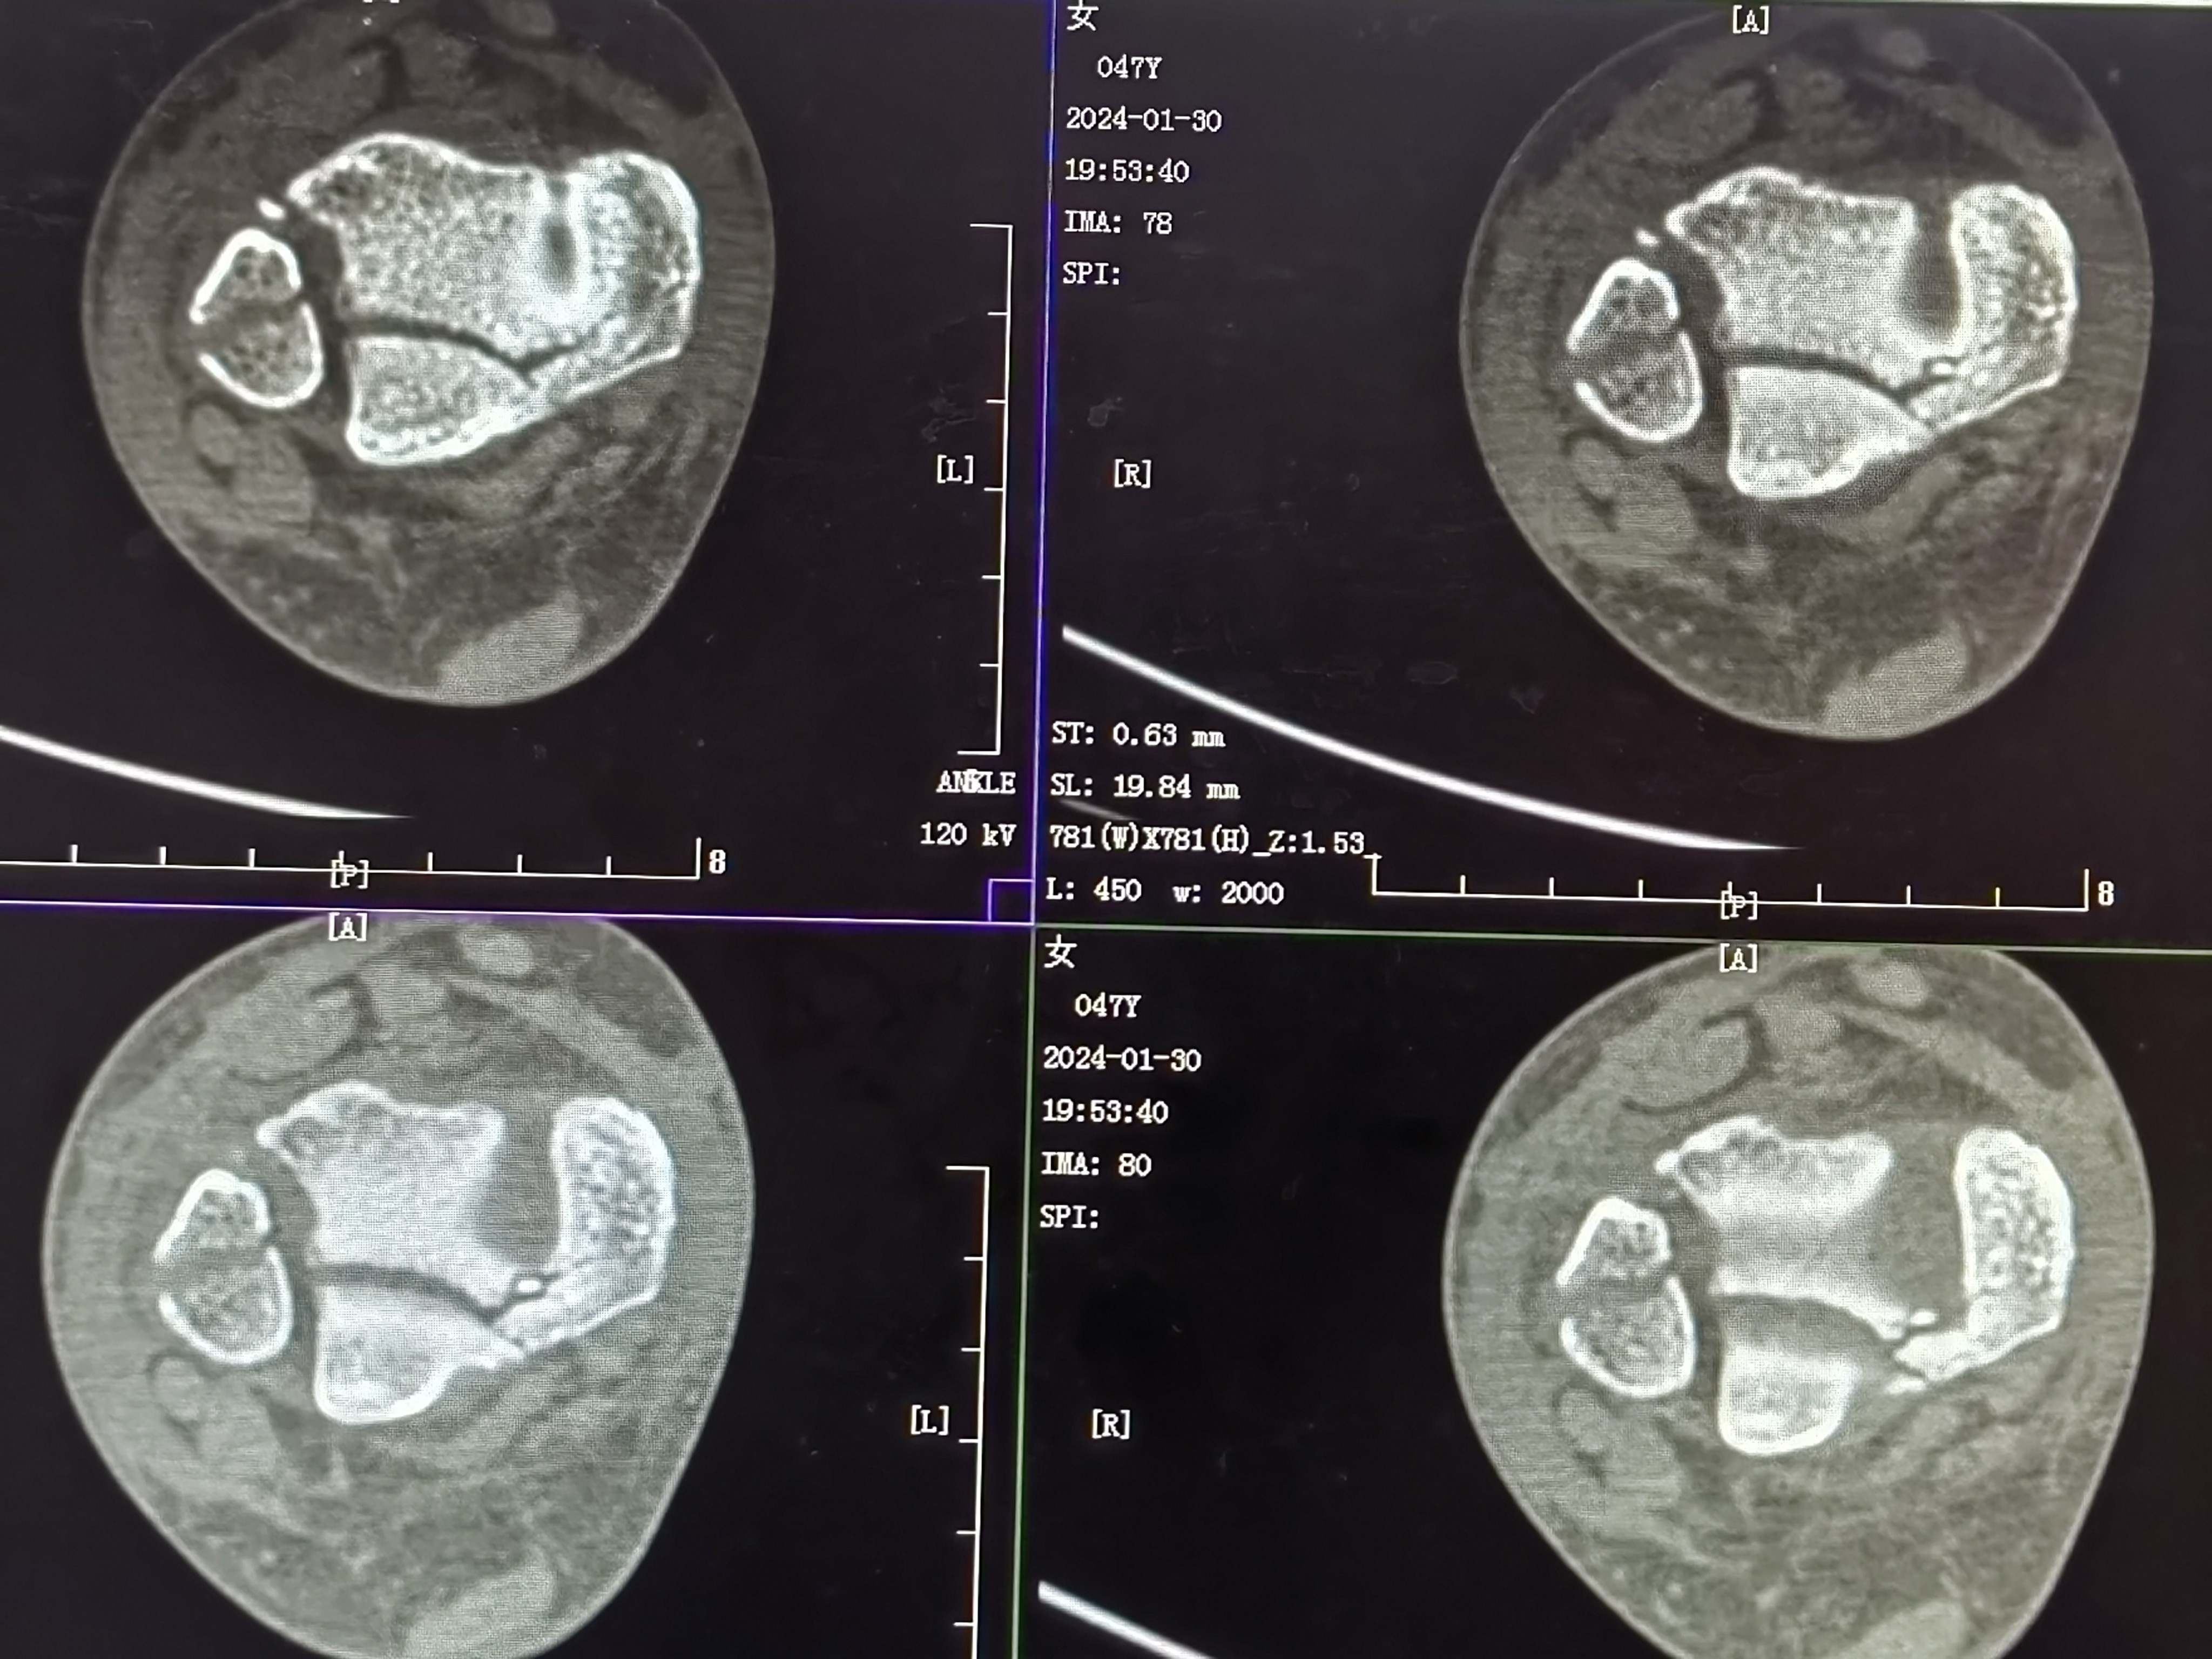

复位后

3天复查CT

关节面台阶约1.0mm